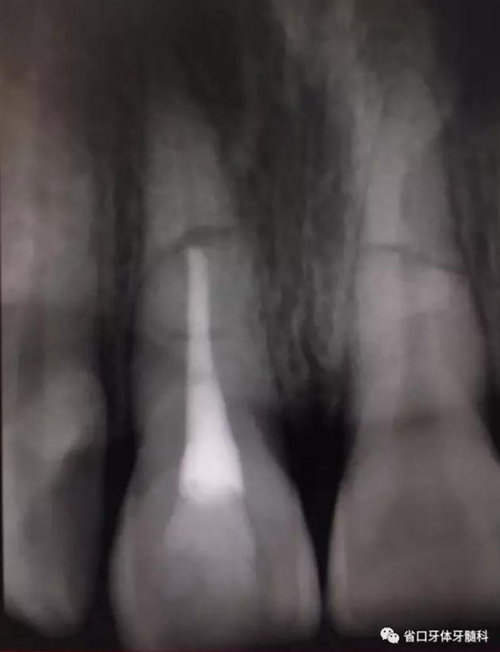

處理:11橡皮障隔濕,顯微鏡下開髓,揭髓室頂,K銼疏通根管,拔髓,測長度(到根折斷端處)17mm,顯微鏡下鎳鈦預備根管,按工作長度預備根管至60#,沖洗根管,吸干,顯微鏡下MTA斷端封閉,髓腔內(nèi)放置半飽和蒸餾水棉球一個,玻璃離子臨時充填。

圖6 斷端MTA封閉術后